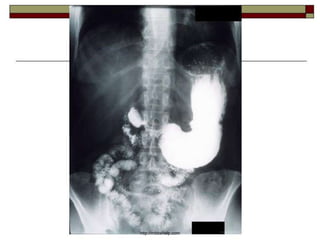

Imaging Studies and Other Tests

A chest x-ray may be useful to detect free

abdominal air when perforation is a possibility.

A CT scan is only useful when other conditions

are being considered.